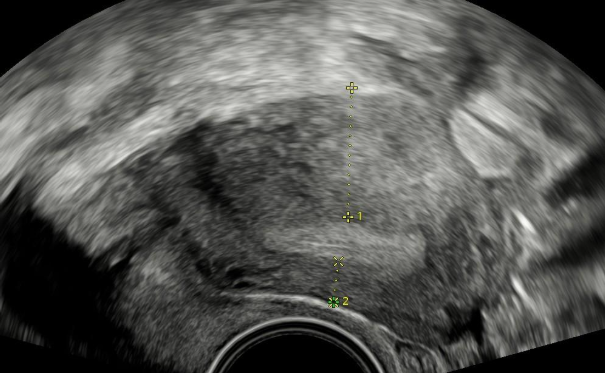

Ultrazvuk: dvoukomorová endometriózní cysta vaječníku.V praxi jsem se velmi často setkával s klientkami, které za sebou měly několik operací pro bolesti v podbřišku nebo neplodnost a jejich obtíže přetrvávaly po operaci dále. Ložiska endometriózy, zvláště ta hluboká, byly často přehlédnuta, nebo je operační tým neuměl vyřešit a žena tak zbytečně podstoupila další operační zákrok. Našim cílem bylo (a je) klientku správně vyšetřit a pokud si řešení vyžádá operační intervenci, tak odstranit všechna ložiska, která způsobují problém.

Adenomyóza dělohy. Nápadná rozdílná šířka stěny děložní svaloviny.